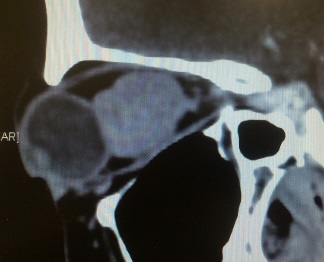

Orbital Tumour Surgery

Any tumour mass can occur within the bony socket of the eye. It may occur as a primary tumour or secondary tumour (metastatic disease). It is also essential to know the difference between a benign and malignant tumour. After discussing the symptoms and signs, a detailed clinical examination and some clinical tests, Dr Nazila will order for an imaging such as CT scan or MRI and advise for surgery.